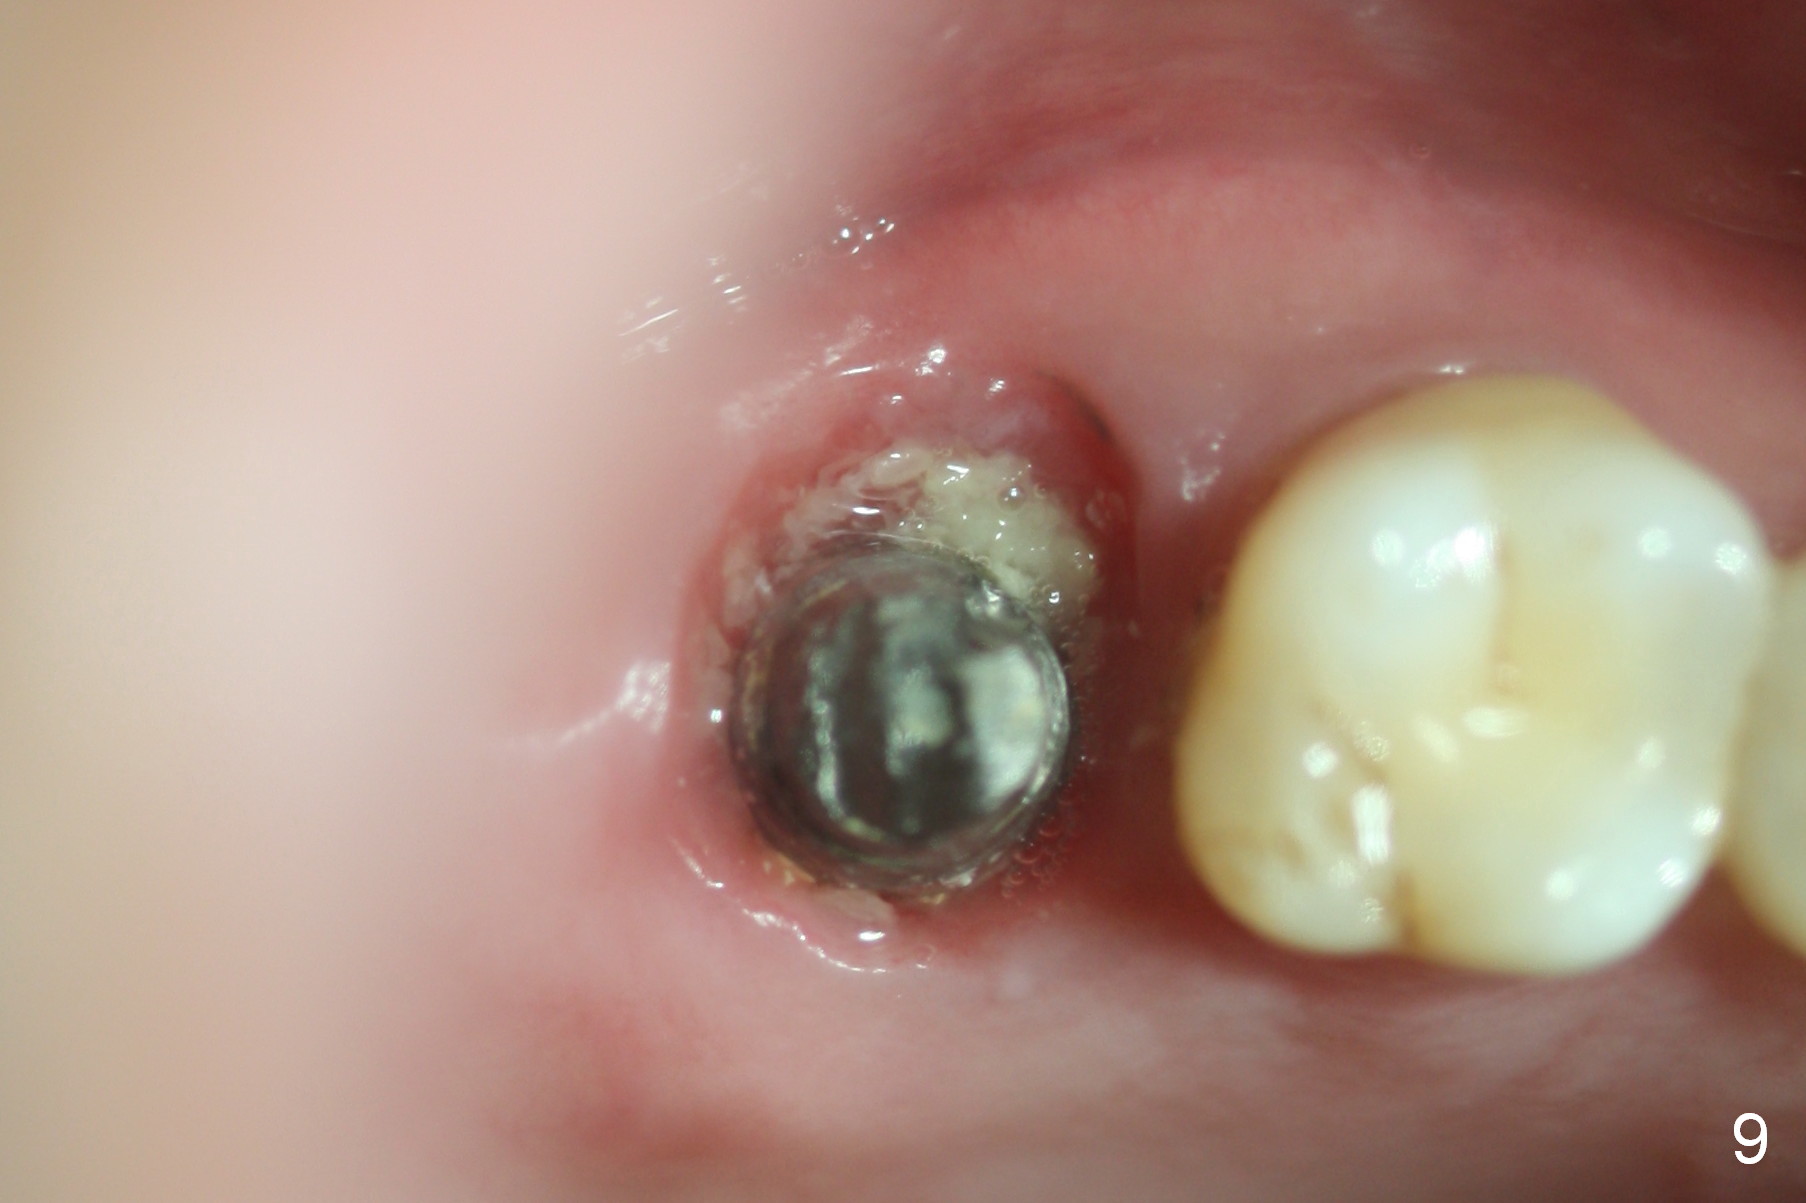

The patient returns for follow up 1 week and 1 month postop. The provisional remains in place. It is removed for margin modification 1 month postop: the bone graft having been apparently incorporating into the socket concentrically (from periphery of the socket to the implant) (Fig.9).